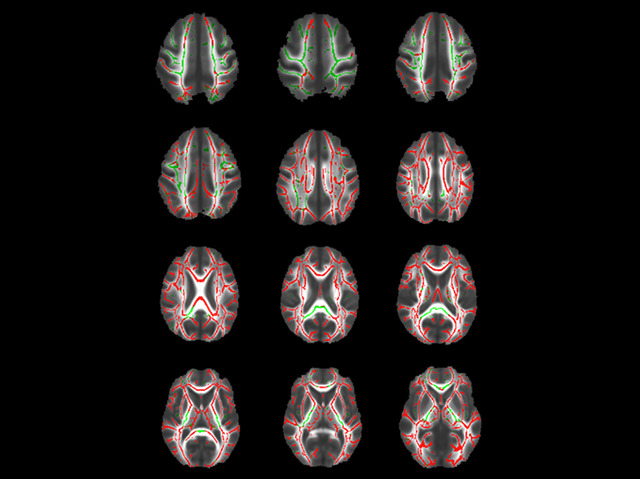

No, not the latest design in bicycle helmets; rather these are brain images taken from a study researching the ageing process. The brain consists of two distinct regions: grey matter, containing the operational centres of brain cells; and white matter – the long nerve fibres that extend into the body. We already know that grey matter shrinks as we get older but what happens to the white matter? To find out researchers scanned the brains of around 350 adults with magnetic resonance imaging (MRI) and used computer software to merge the images. From this they created a composite 3D map that shows the typical location of white and grey matter. In the picture the distribution of white matter is highlighted in green while the regions that are smaller in the elderly are shown in red. So some, but not all, of the white matter shrinks with age.